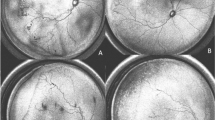

FFA has been a useful adjunct to clinical examination in pediatric retinal vascular diseases. Widefield FFA helps to document and analyze subtle peripheral vascular changes that can be missed on clinical examination (Fig. 5.2). Retcam 3 and Optos 200Tx have been successfully used to record widefield angiograms in infants [20, 37]. FFA has helped identify vascular abnormalities such as areas of non-perfusion, extent of neovascularization, avascular loops, residual skip areas, and status of macular perfusion in APROP [20, 37].

Wide-field retcam fundus photographs in a preterm infant born at 28 weeks of gestation with a birth weight of 1000 grams showing flat neovascularization or hemorrhage in posterior zone II with pre-plus. (a, b). Fluorescein angiography confirms and also demonstrates the extent of neovascularization at the vascular avascular junction (c, d)

Anti-VEGF therapy is preferred over laser in infants with severe vaso-obliteration and vascularization limited to posterior zone I (Fig. 5.3). Fluorescein angiography helps to clearly delineate persistent avascular retina following treatment with Anti-VEGF agents and helps guide the need for retreatment and follow-up.

Retcam fundus photography showing posterior zone I APROP with loops and shunts in posterior zone I (a, b) along with a preretinal bleed over the optic disc (b). Fluorescein angiography confirms non-perfusion of the macula in both eyes (c, d). This infant was treated with Anti-VEGF therapy to provide an opportunity to allow vascularization to progress beyond macula